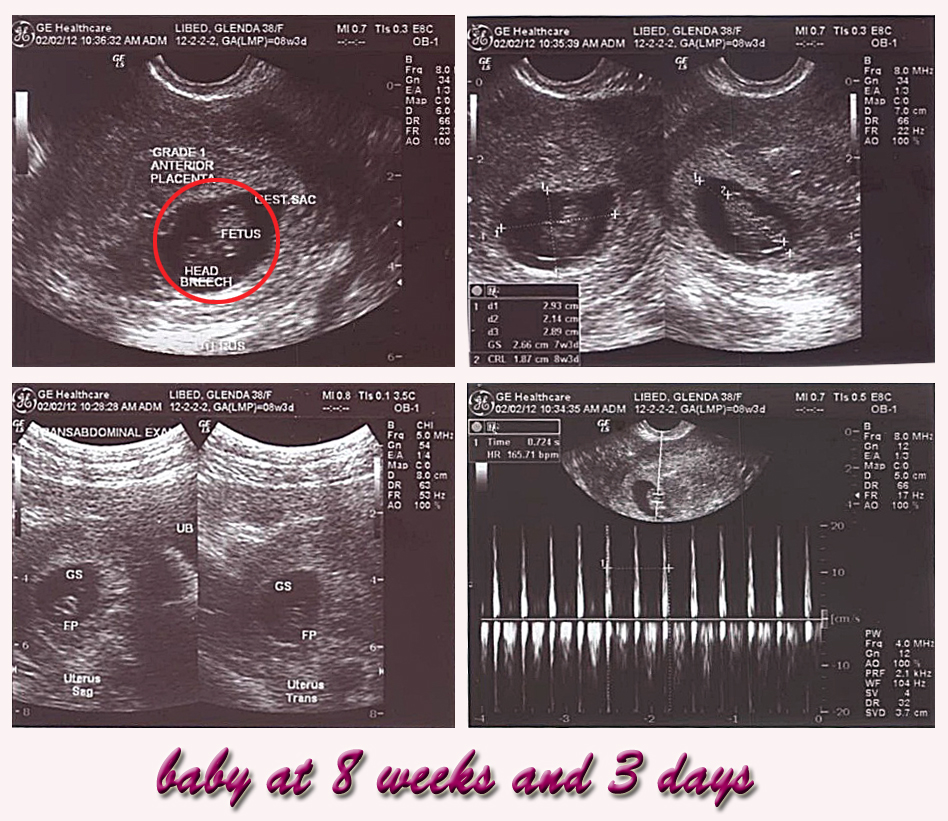

Now it is my challenge when I become one.  At this time, I could care less about the responsibilities of motherhood (I don’t want to fill my mind with anxieties of the future). I will contain and focus on  how I could take care of myself so that this tiny “someone”…my baby (hmmmm fetus hahahha) will have to get enough nourishment in a day.  I and my husband are so conscious of what I eat such that we both check vitamins contents of what I take in.

Aside from that I now have some small interaction with him / her  (our baby) when I am alone in the house ( or even if my husband is around),  through stories and music.  I talk and touch my tummy.  I do explain everything including what mommy did in a day and why I am tired, how I am feeling, why mommy is laughing, what strange things I am seeing.  I explain the excitement of why it is good to come out soon with where I am and many more.  I share that daddy and mommy are so happy with him / her.  That he / she is our greatest surprise this year.  I tickle my tummy too. And that I would do anything I can to give him / her the best formation I could extend (perhaps because I just love to write training modules that my baby will soon become a recipient ….hahahahah).

A friend, Doctor – Ronnie Bongocan (my sister’s brother in law) advised me to take my test this weekend (January 22).  Exactly the same date as advised by my two sisters.   But then out of our great excitement and my stubbornness, I took the test last Monday (January 16)  placing the kit in front of my husband on the table.  It was such a wonderful sight of a positive test.  Voila…I AM PREGNANT!!!!!!!

From there, I went straight to my computer to do some module writing which I could hardly focus on since I felt conscious already of “someone”…a beautiful tiny creature in my tummy taking its form right where I was.  I just decided to stop writing and pulled some CDs including a CD on nursery rhymes and thought of putting them inside a USB storage device and listen to it from time to time.  Well my husband just stopped me from my excitement and told me to relax.  I was a little stubborn and still did it  ( hahahhaha crazy ha).

Well you could imagine me now starting to do that with my earphone –one for me and one on my tummy -…hahahha well there is more to this in the coming days….

I guess…I could park for now preparing for more future details …with how I am dealing with myself and the doctor’s appointment and the regimen of vitamins, food, and …of course …exercise… (my baby held on even when I had the most of those jogging and walking)… plus the love and support  from my husband.